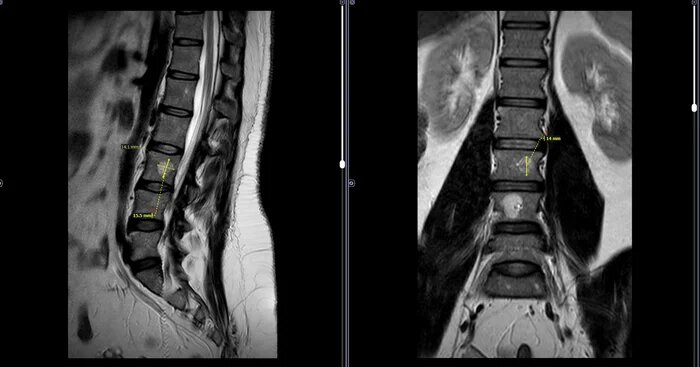

МРТ-Гемангиома тела L3 позвонка, очаг жировой дегенерации L4⁠⁠

В теле L3 позвонка определяется гемангиома, размером 15х14х14мм, без перифокальных изменений. В теле L4 позвонка определяется очаг жировой дегенерации костного мозга, размером 20х16х8мм.

С учетом средних размеров гемангиомы тела L3 позвонка, частого обострения болевого синдрома, категория годности по ст.10(Доброкачественные новообразования)б-В(ограниченно годен к военной службе).